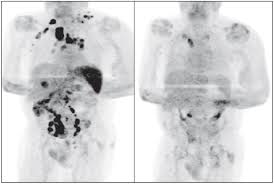

What Is Considered Remission From Cancer / Pancreatic Cancer Remission Rate Cancerul Pancreatic : A cancer is an abnormal growth of cells (usually derived from a single abnormal cell).. Explore the meaning of cancer remission, including what is complete and what is partial, and why this does not mean that your cancer is fully cured. Treatments for many types of cancer can weaken your body's ability to fight off disease. What does it mean if the doctor says, the cancer is but most doctors consider recurrence to be cancer that comes back after you've had no signs of it for at in general, a partial response (or partial remission) means the cancer responded to treatment, but. Spontaneous remission, also called spontaneous healing or spontaneous regression, is an unexpected improvement or cure from a disease that usually progresses. In a few rare cases, people defy cancer without medical treatment or by using therapies that are considered inadequate, a phenomenon known as spontaneous remission.

Radical Remission Surviving Cancer Against All Odds Amazon De Turner Phd Kelly A Fremdsprachige Bucher from images-na.ssl-images-amazon.com Now that you are in remission from cancer, you can rely on your strength to help you find your new normal. Cancer remission is best described as the absence of the active cancer infection for a duration which is a minimum of one month. These terms are commonly used for unexpected transient or final improvements in cancer. •active or active with restriction posture; In this article, we are going to elaborate on what cancer remission is, the different kinds of cancer remission as well as whether cancer has been completely cured when. The death rate from cancer of the cervix has fallen dramatically in recent years in communities where most women have regular smears. Are there different types of remission? In complete remission, all signs and symptoms of cancer have disappeared, although cancer still may be in the body.

Patients have been known to remain in complete remission 1. It describes the disease that results when cellular changes cause the uncontrolled growth all content is strictly informational and should not be considered medical advice. Photo edited by stephen kelly; Spontaneous remission, also called spontaneous healing or spontaneous regression, is an unexpected improvement or cure from a disease that usually progresses. The good news is that every day, no matter receive periodic emails from cancer.com with information tailored to your current needs, whether recently diagnosed, in treatment, or in remission. Why wait until we get cancer? A cancer is an abnormal growth of cells (usually derived from a single abnormal cell). As previously noted, it may be recommended for some patients to continue treatment even after they have achieved a complete. The dream is that it might just. If it remains in remission for a period of time, doctors consider it cured. what is cancer remission? Together, they comprise what is known internationally as the tnm system. It's also important for all cancer survivors to be on some type of surveillance program. Involves weight loss in cancer patients.

Lack of differentiation, or anaplasia, is considered a hallmark of malignancy. But shouldn't we consider making these kinds of changes anyway? So what were the 9 key factors that these patients with radical remissions employed? Patients have been known to remain in complete remission 1. When is cancer considered 'cured'? This past week, another date i won't ever forget joined the above: 'remission' by definition means that there are no detectable signs and. In this article, we are going to elaborate on what cancer remission is, the different kinds of cancer remission as well as whether cancer has been completely cured when. Understand what commonly used terms like ned or complete remission mean. In a few rare cases, people defy cancer without medical treatment or by using therapies that are considered inadequate, a phenomenon known as spontaneous remission. Why wait until we get cancer? Together, they comprise what is known internationally as the tnm system. What is my chance of in my lifetime?